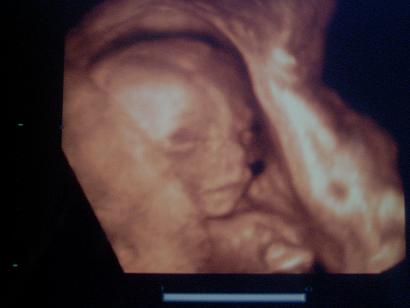

Sajnos képet nem kaptunk, mert elég futószalagszerűen ment, meg nem is a dokim uh-zott, de majd a 24.-25. héten megyek 4d-re, majd ott kérek képet, videót, mindent!